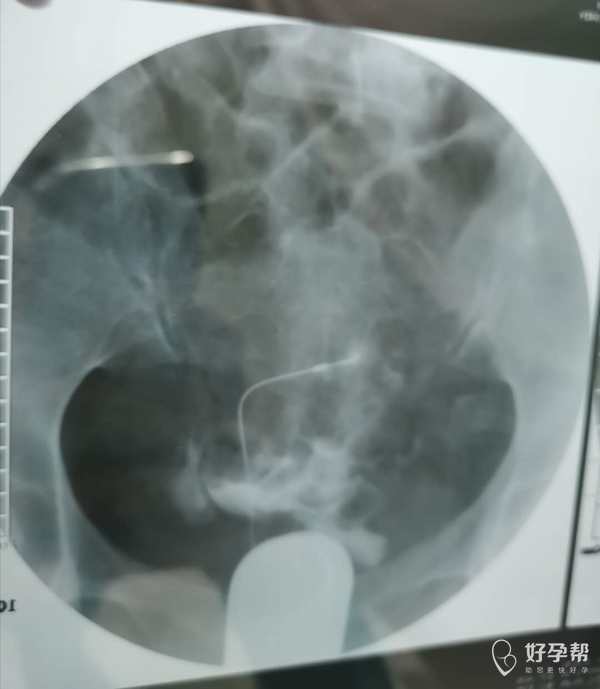

我这个是做了输卵管介入手术,请问输卵管是通了

你的片子提示双侧输卵管不通,未孕4年,合并腺肌症和腺肌瘤,建议你直接试管婴儿助孕。试管前不需要宫腹腔镜检查。